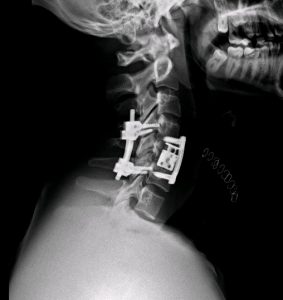

Accidente tráfico. Politrauma. Fractura cervical C5 inestable con compresión medular

Se realizó corpectomía C5 con reconstrucción anterior en un primer tiempo (prótesis expansible + placa cervical). En el mismo acto, se dio la vuelta al paciente y se realizó una fijación posterior para asegurar el montaje (dadas las lesiones ligamentosas asociadas).